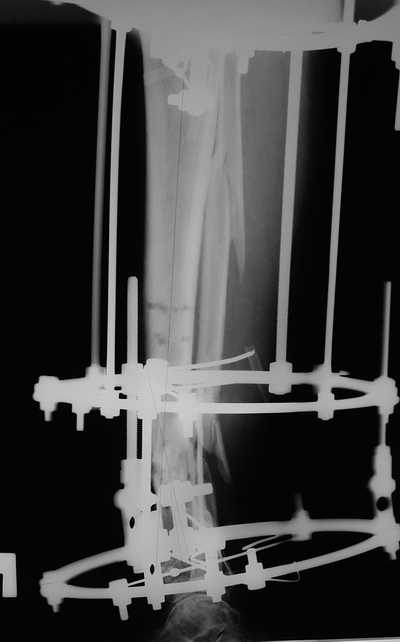

Женщина 46 лет, неудачно лечившаяся по поводу перелома голени в нижней 1\3 сначала в гипсе, поступила через 6 месяцев после остеосинтеза пластиной (рис 1). Имелась деформация в нижней 1\3 голени: варус, антекурвация, наружная ротация, два свища. Удалена пластина, дебридмент мягких тканей,

остеотомия м\б кости, аппарат Илизарова. По рентгенограммам в двух проекциях произведено планирование устранения смещений (рис 2 и 3), между вторым и третьим кольцом установлены 6 телескопических дистракторов Гесапода, данные введены в программу, и далее втечение 10 дней больная подкручивала телескопы согласно выданной компьютером инструкции. По завершению репозиции гексаподные телескопы обратно заменены на обычные штанги от аппарата Илизарова (рис 4 и 5). Еще через две недели забит гвоздь (рис 6, контроль

через 4 месяца).